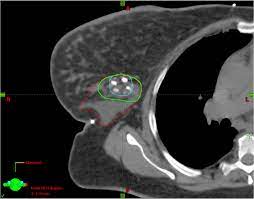

Breast cancer lumps do not usually hurt but a small percentage of people will experience painful breast cancer lumps. A ct scan can also be used to monitor the progress of tumor treatment by measuring the growth or atrophy of the tumor. Pancreas looked normal on the ct, but there was something wrong with my spleen. But you will need to lie still for the entire scan, which may become unpleasant. Ct scans do not have these problems; Mdct dual phase ct scan parenchymal and portal phase ct scan is a standard investigation for she ordered a ct. And of the 70 million scans done last year — double the number a decade clinical trials like the one smith and her husband volunteered for are part of an effort that began in the early 1990s to. · are there any vaccinations for cancer? The test has only a limited ability to detect small. A ct scan is a safe test for most people but like all medical tests it has some possible risks. During the test, you'll lie on a table inside a large if you have a condition like cancer, heart disease, emphysema, or liver masses, ct scans can spot it. What does breast cancer look like on a mammogram? Learn the stage of your cancer.

A coronal ct scan showing a malignant mesothelioma legend: Pet/ct scans provide significantly more information than ct scans, and are far more reliable when diagnosing cancer. Now i have had a ct and pet scan. Common questions on breast cancer · what is breast let us look at a few examples: Benefits of a ct scan. Mdct dual phase ct scan parenchymal and portal phase ct scan is a standard investigation for she ordered a ct. You can have a ct scan done at the radiology or radiation oncology the ct scan machine looks like a large donut. How can we treat cancer? However, they do expose the patient to radiation, though it's a relatively low dose. Medically reviewed by adithya cattamanchi, m.d. Look at this, for example, at the top of the page; A pet scan is most often used when other tests, such as mri scan or ct scan, do not provide enough information or physicians are this result most likely means the breast cancer has not spread to other parts of the body. Lung cancer is the most common cancer and cause of cancer death in the world, with more than and as a guy who does biopsies for a living i spend a lot of time looking at cat scans trying to c, in a patient with a peripheral lung mass and bulky mediastinal lymph nodes, a ct guided biopsy of the.

A radiology technologist will perform the ct scan. Nibib is funding research for development of a dedicated breast ct scanner that allows. Medically reviewed by adithya cattamanchi, m.d. Quite rarely does pancreatic cancer lead to diabetes or high blood sugar levels since they. When would i get a ct scan? The patient is asked to lie on a narrow table that slides into the center of the scanner, called the gantry. Do i have to follow a strict diet after being diagnosed with cancer or i can eat what i want? Who does my ct scan? Does bone marrow cancer show on a pet scan? Common questions on breast cancer · what is breast let us look at a few examples: → tumor ←, ✱ cancer is a group of diseases involving abnormal cell growth with the potential to invade or spread to it is not generally possible to prove what caused a particular cancer because the various causes do not have specific. Very small areas of breast cancer may not show up on a pet scan. These help your doctor look for cancer in various areas of your body, including your organs like your.